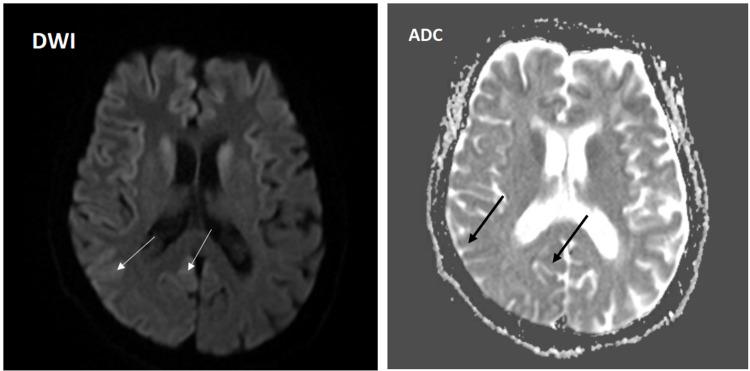

Creutzfeldt-Jakob disease (CJD) is a rare, fatal brain infection caused by a human prion. Because CJD is associated with rapidly progressive neurological degeneration, it requires high suspicion for diagnosis. We report the case of a 79-year-old patient who presented with a rapidly progressive neurological clinical picture. The patient had positive 14-3-3 proteins in cerebrospinal fluid, electroencephalography was significant for periodic discharges, and magnetic resonance imaging of the brain showed both diffusion restriction and increased fluid-attenuated inversion recovery signal in different cortical regions, consistent with probable sporadic CJD infection. The patient was enrolled under hospice and palliative care. The patient passed away two months after the onset of her symptoms. We discuss the probable sporadic CJD diagnostic criteria and possible risk factors that might have led to a faster progressive course.

克雅氏病(CJD)是一种由人类朊病毒引起的罕见致命性脑部感染。由于CJD与快速进展的神经退行性变有关,因此诊断时需要高度怀疑。我们报告了一例79岁患者,其临床表现为快速进展的神经系统症状。该患者脑脊液中14-3-3蛋白呈阳性,脑电图显示有周期性放电,脑部磁共振成像显示不同皮质区域既有弥散受限又有液体衰减反转恢复信号增强,符合可能的散发性CJD感染。该患者接受了临终关怀和姑息治疗。患者在症状出现两个月后去世。我们讨论了可能的散发性CJD诊断标准以及可能导致病程进展更快的危险因素。